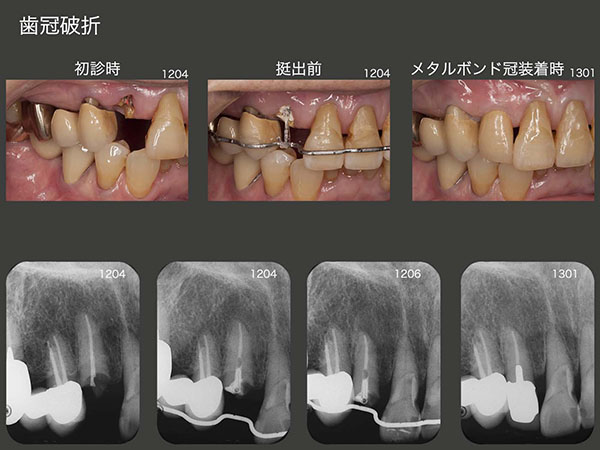

2.歯冠破折

2012年4月初診,79歳の女性.右上3が折れたとのことで来院.歯冠部の歯質はないが,デンタルX線写真から歯根には十分な長さの歯質がある.もし抜歯となりブリッジを製作するとなれば,右上⑥5④の既存ブリッジを作り直すことになるし,ほぼ健全歯である右上1を切削する必要が生じる.このような大掛かりな治療を行わず,右上3の保存に努めるべきである.そこで,4月に矯正的挺出を開始し,6月に終了した.その後歯冠長延長術を行い,歯肉縁上歯質を確保した.暫く経過をみて特に問題が生じなかったので,13年1月にメタルボンド冠を装着した.